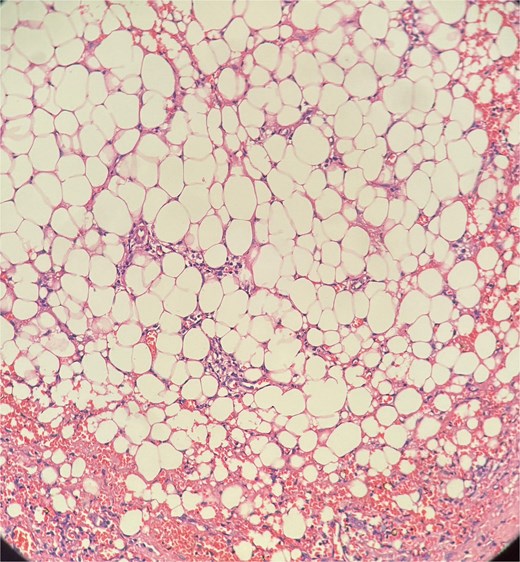

The patient underwent examination under anesthesia and exicision and biopsy (Fig. 4) of the extra-luminal growth via perianal route under spinal anesthesia. A curvilinear incision was made in the right perianal region from 7 o’ clock to 11 o’clock position, 1 cm away from the anal verge to access the tissue, which was then excised in toto and sent for histopathological examination. The cavity was left open to heal by secondary intention. Histopathological examination (Figs 5–7) which was a definitive diagnosis revealed features suggestive of panniculitis. This was the key diagnostic test, confirming perianal panniculitis rather than a fistula or malignancy.

Picture depicting evidence of fat necrosis in the excised perianal tissue.

Sections show a dense inflammatory infiltrate within the subcutaneous adipose tissue, consistent with panniculitis. The infiltrate is composed of neutrophils, lymphocytes, plasma cells, and histiocytes.

Histopathological examination showed ghost-like adipocytes and foamy histiocytes.